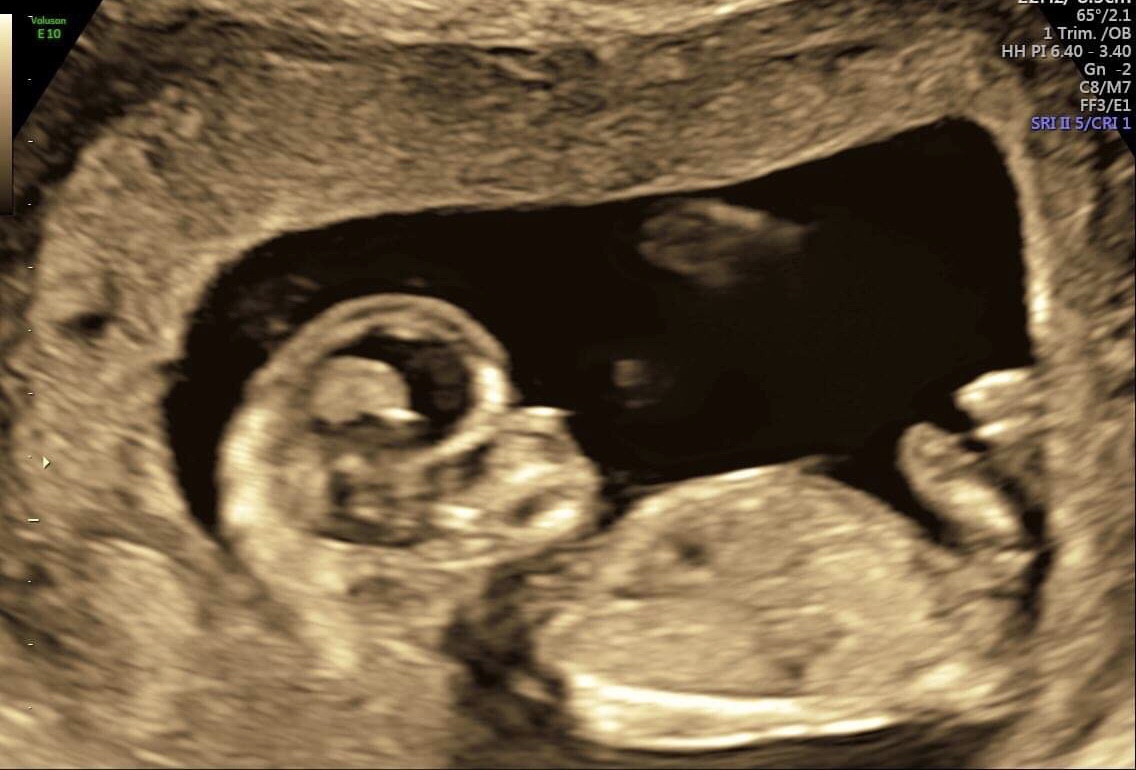

Thx - here a some pics Attachment 41968

Still thinking girl

tentative pink lean but not the best for guessing for me

The nub seems flat, which is more pink friendly, but the shape and length seem somewhat boyish and makes me wary to sign off on it totally being a girl. Slight pink lean.

The other one started off with the baby facing away, but it turned over midway through. I would give a tentative pink lean (like 52%/48% LOL) but the nub was only visible for a moment, and the baby was in motion when I thought I spotted it, so I don't have much confidence that I can guess accurately. The baby being in motion means that the angle of the dangle is not at all reliable and I just don't like getting anyone's hopes up when I can't give an accurate guess.

Still a girl lean from me

The nub looks girly

I have the same problem I had before - I feel like the nub is awfully short for a girl. It's pretty straight, but at the same time it's not that clear cut obvious girl nub. I'm still about 50-50 with a slight pink lean due to what I saw on the video.

these photos which look a bit "orange" (not black/white) are from my 1st trimester screening at a praenatal diagnostic - i hoped he tells me gender, but he didnt... so these are original photos taken at 12+4